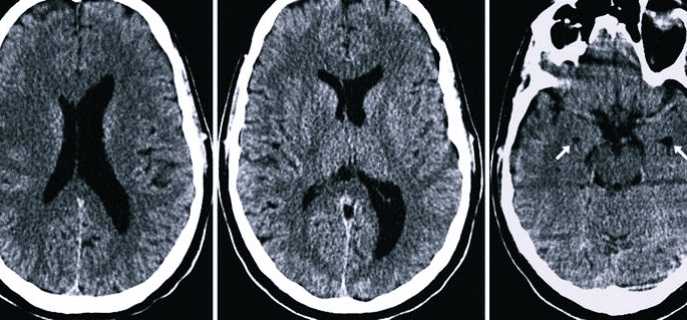

Подтвердить наличие асимметрии боковых желудочков можно, пройдя компьютерную томографию, магнитно-резонансную томографию, нейросонограмму, офтальмологическое обследование глазного дна, пункцию ликворной жидкости.

Нарушается отток цереброспинальной жидкости при перекрытии ликворного пути опухолевидным новообразованием или кистой. Расширение боковых желудочков происходит на фоне травмирования головы, развития идиопатической гидроцефалии, присутствия посттравматической гематомы. Также расширение структур может быть вызвано геморрагическим инсультом, тромбозом центрального сосуда.

Асимметрия боковых желудочков головного мозга может проявляться различными неврологическими симптомами, включая головные боли, нарушения координации, проблемы с памятью и вниманием. Врачи отмечают, что данное состояние может быть связано с различными патологиями, такими как травмы головы, инсульты или врожденные аномалии. Для диагностики асимметрии используются методы нейровизуализации, такие как МРТ, которые позволяют точно оценить размеры и форму желудочков.